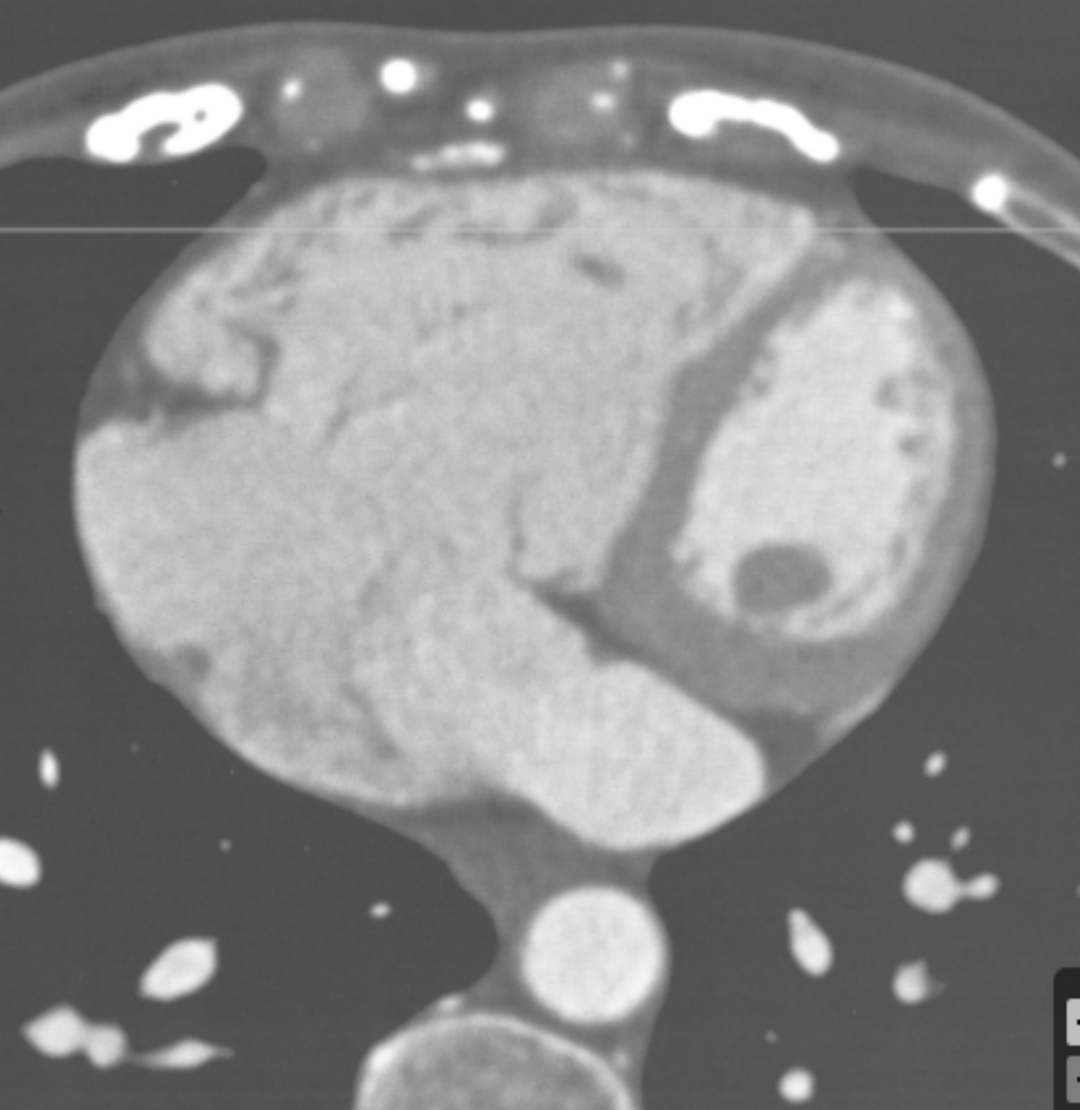

Describe the findings

Persistent L SVC

Unroofed coronary sinus (CS) –> enlarged RA, RV, dilated coronary sinus